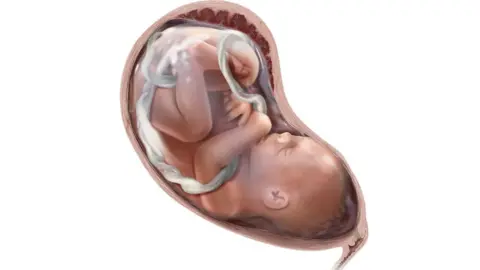

Getty ImagesSpina bifida and foetal repair surgery

Spina bifida literally means 'split spine', and occurs when the spinal column and cord are not properly formed in pregnancy (before the sixth week) - leaving nerves exposed.

It occurs in around four in 10,000 pregnancies.

The cause is unknown, however mothers are encouraged to take folic acid supplements to reduce the risk of developing spina bifida in early pregnancy.

Babies born with the condition can become paralysed, suffer bladder and bowel problems - and it can affect brain development.

It is estimated that about 80% of mothers choose termination when spina bifida is diagnosed, although the condition varies in severity.

The delicate surgical procedure involves opening the uterus and closing the gap in the baby's back while they are still in the womb.